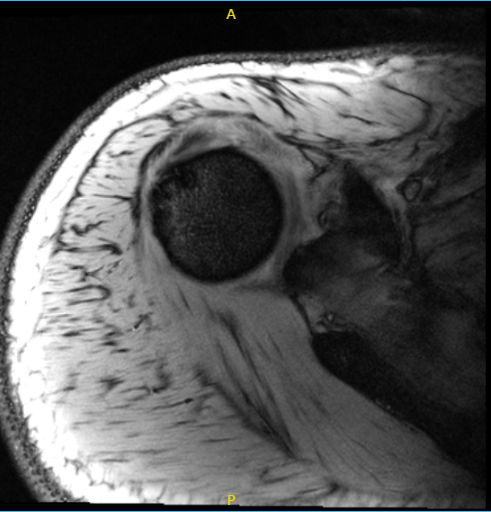

His MRI showed an impression as follows: Focal grade 1 partial-thickness tear of the infraspinatus tendon at the footprint with adjacent small traction cysts. Intact labrum and biceps tendon. Widening of the AC joint suggestive of chronic AC joint separation versus a previous. Mumford procedure. Correlate with surgical history.

MRI of the right shoulder